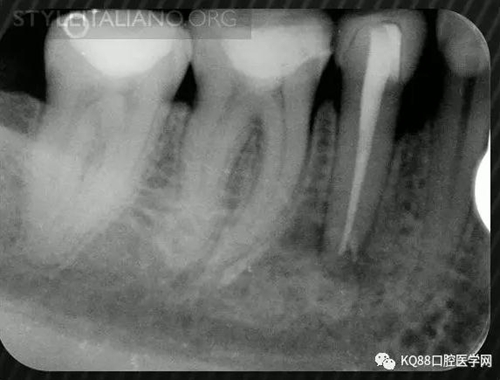

Case 1: In this patient, persistent pain was present after endodontic treatment of a vital tooth. The periapical x-ray showed an inadequate shaping of the distal root canal, regarding both the working length and the apical taper.

Img. 2 - Retreatment of distal canal was performed using ProTaper retreatment files. Working length was assessed electronically. Canal was shaped with a Reciproc R40, thoroughly irrigated with US activation, filled with corresponding Guttafusion obturator. Pain disappeared completely some days after retreatment. In all likelihood, incomplete preparation allowed residual pulp tissue to remain in the root canal, acting as an irritant.